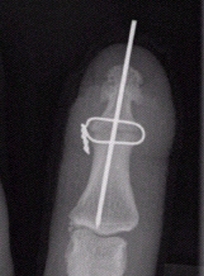

- Die Versteifung des betroffenen Gelenkes in einer guten Gebrauchsstellung. Dabei wird das zerstörte Gelenk entfernt und die benachbarten Knochen durch Drähte oder eine Schraube in achsgerechter Stellung fixiert. Nach einer ca. einstündigen Operation wird der Finger für drei bis sechs Wochen ruhiggestellt bis der Knochen verheilt ist. Diese Operation kann ambulant durchgeführt werden. Nach knöcherner Durchbauung ist der Finger schmerzfrei wieder kräftig einsetzbar. Diese Operation kommt hauptsächlich für das Endgelenk in Betracht.